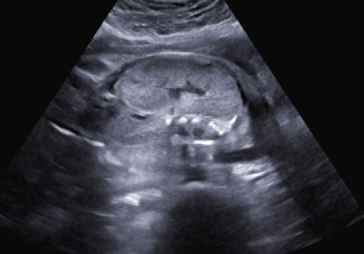

Ein zunächst durchgeführtes CTG war unauffällig. Im Rahmen der sonografischen Untersuchung zeigte sich der Fötus soweit beurteilbar zeitgerecht entwickelt. Dennoch konnte ein Anhydramnion festgestellt werden(Abb. 1, 2), weshalb auch kein fetales Gesicht darstellbar war (Abb. 3).